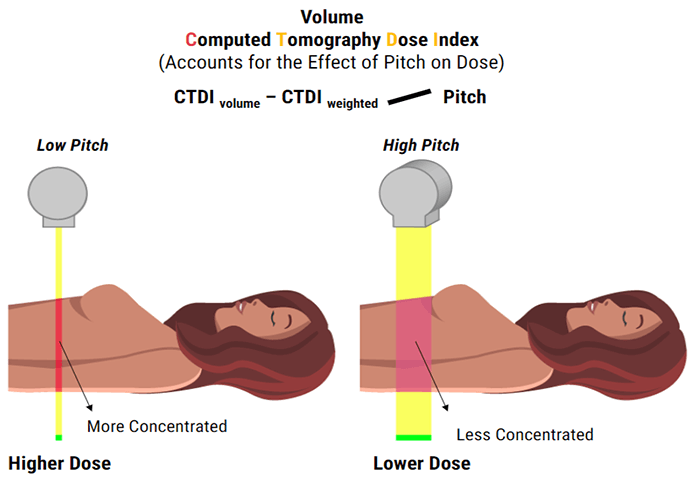

Computed tomography dose index (CTDI)

Computed Tomography Dose Index, known as CTDI, currently is not used but was the original equation used to calculate the patient dose in CT. It was developed by the Federal Drug Administration (FDA)and represents the mean absorbed dose in a scanned object measured in Grays. There is also CTDIv or volume which can be used to calculate dosage from a spiral scan per slice of tissue. Some feel this method may undervalue the dosage given to the patient. The CTDIv is defined by using an acrylic phantom and is not a dose to any actual patient.

PITCH

Spiral pitch or helical pitch is defined as the ratio of the distance the table travels per rotation to the total collimated x-ray beamwidth. It can also be defined as an extension or contraction of the helix. The pitch has an inverse relationship to the dose. If the Pitch increases by 2, the dose is reduced to one half. It affects not only patient dose but image quality as well.